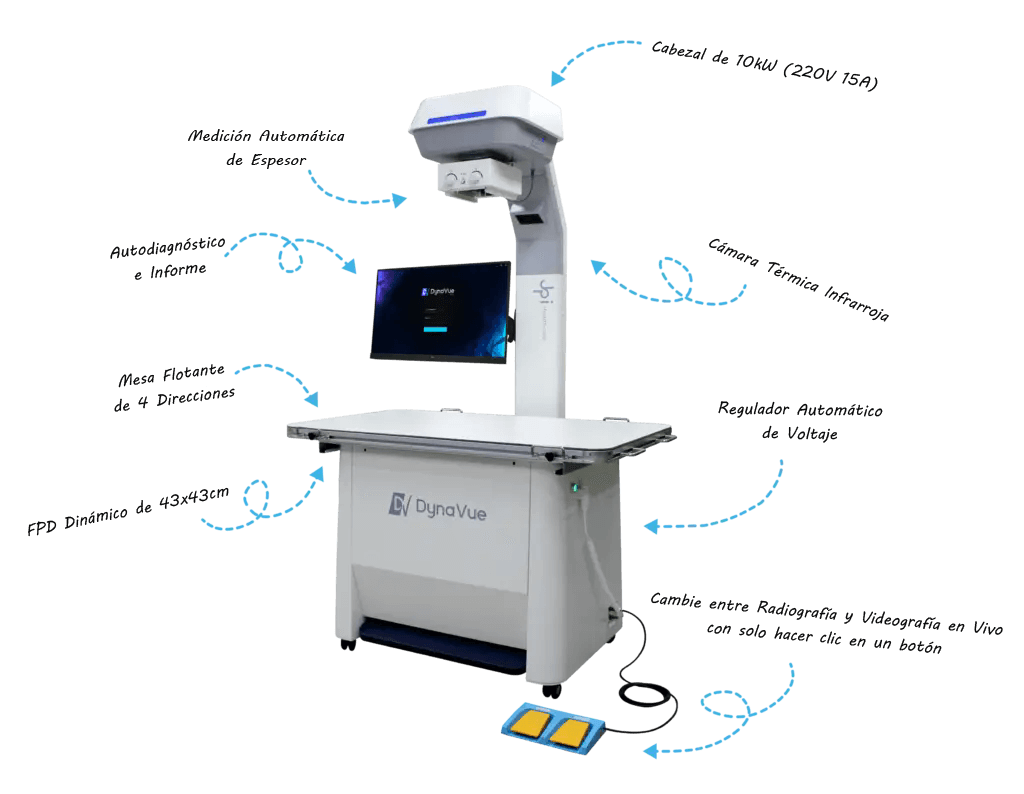

Imágenes Térmicas

Medir la variación de temperatura para ayudar a identificar áreas de posible enfermedad.

Sensor LIDAR

Mida el grosor del paciente y establezca las técnicas adecuadas automáticamente.

Fluoroscopía

Mejore los diagnósticos y las intervenciones capturando imágenes en tiempo real con Fluoroscopía de alta velocidad y baja dosis.

Todo en Uno, Fácil de Usar.

Vea más, diagnostique más rápido

Vista en Vivo Interactiva

La cámara en vivo ayuda a posicionar al paciente, lo que le permite ver y grabar el estudio en tiempo real. Puede operar el software desde una estación de trabajo remota ubicada en otra habitación.

Detección Avanzada de Temperatura

El sistema de imágenes térmicas mide la variación de temperatura en el paciente, lo que indica posibles lesiones e infecciones.

Técnicas Adecuadas Automatizadas

Con el sensor LIDAR incorporado, el sistema ATD (Detección automática de espesor) mide el espesor del paciente con precisión y proporciona automáticamente las técnicas adecuadas para usted.

Calidad Superior de Imágenes

DynaVue™ Duo es un equipo de rayos X digital de alta gama que ofrece una calidad de imagen superior, nítida y muy detallada.

Fluoroscopia DR Inmersiva

La tecnología LVX (Live Video X-ray) mejora el proceso, ofreciendo un amplio campo de visión de 17” x 17” con fluoroscopia de 30 FPS sin necesidad de grandes arcos en C ni mesas de fluoroscopia.